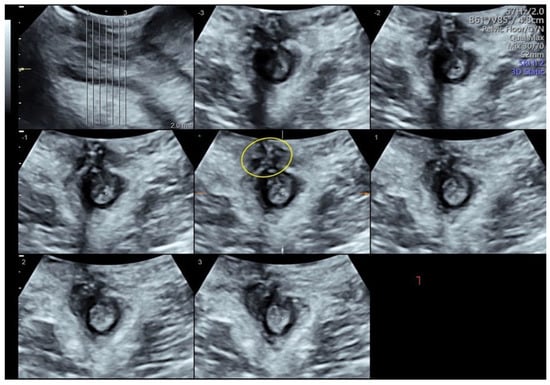

Three-Dimensional Transperineal Ultrasound Guiding Early Secondary Repair of Obstetric Anal Sphincter Injury in an Incontinent Patient without Suture Dehiscence

Orsi, M.; Cappuccio, G.; Kurihara, H.; Rossi, G.; Perugino, G.; Ferrazzi, E.; Coppola, C. Three-Dimensional Transperineal Ultrasound Guiding Early Secondary Repair of Obstetric Anal Sphincter Injury in an Incontinent Patient without Suture Dehiscence. Diagnostics 2024, 14, 68. https://doi.org/10.3390/diagnostics14010068